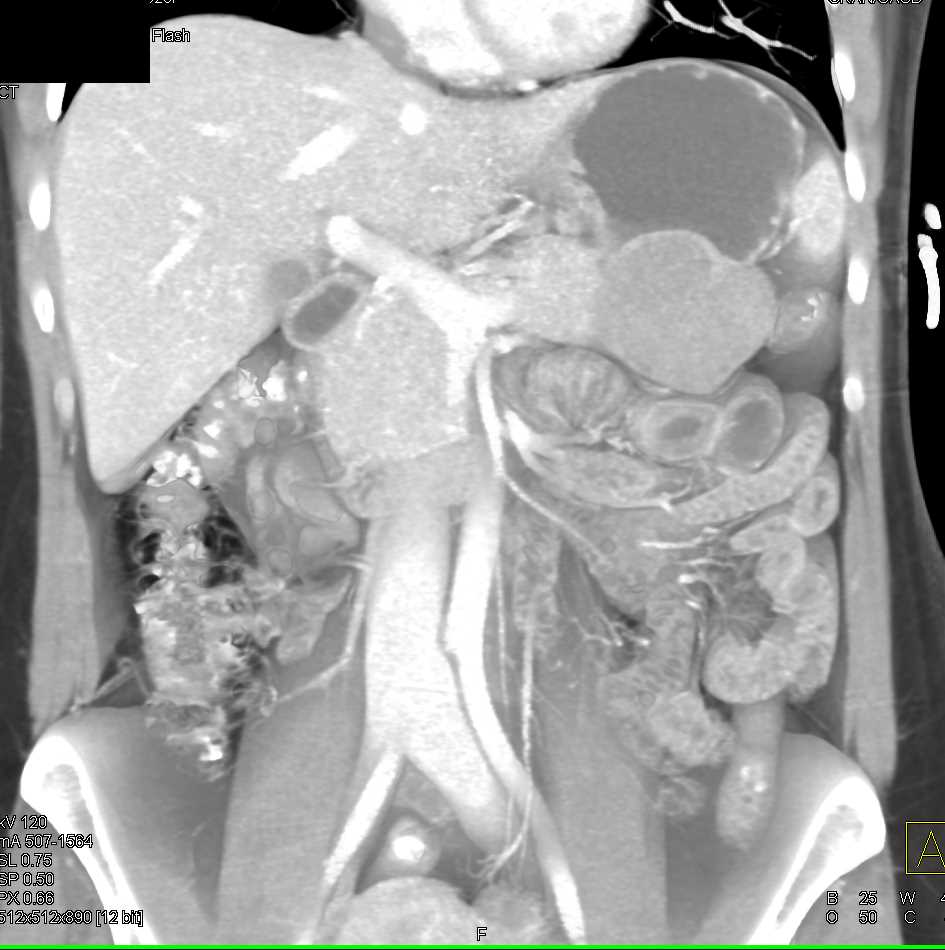

Mass Pushes on Tail of Pancreas was Ganglioneuroma